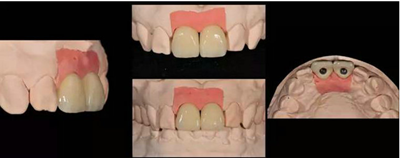

飾面瓷堆塑

牙齒形態(tài)修整

根據(jù)天然牙形態(tài)進(jìn)行牙冠形態(tài)修整、表面紋理再現(xiàn)和咬合關(guān)系調(diào)整

角度螺絲通道全瓷基臺(tái)一體冠制作完成

染色、上釉,再現(xiàn)天然牙的顏色特點(diǎn)。

修復(fù)前

修復(fù)后

本病例中通過對(duì)患者修復(fù)體佩戴后的舌側(cè)、頰側(cè)、左側(cè)、右側(cè)以及微笑照的采集,充分展示修復(fù)體在口內(nèi)的佩戴情況,可以看到無論顏色還是與鄰牙的匹配適宜度都是非常高,也比較吻合年輕女性對(duì)美觀的要求。同時(shí),通過術(shù)后多次隨訪及跟蹤患者后期使用狀況,患者也對(duì)修復(fù)效果十分滿意。